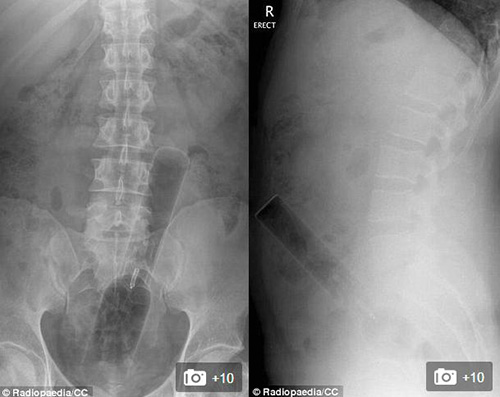

VBF- Đây là các hình ảnh được cung câp bởi các bã sĩ trong bệnh viện. Các bênh nhân sau khi để lọt các đồ vật vào người đã phải đi cấp cứu tại bệnh viện và đã được chụp X-quang để xác định đồ vật đó.Đó thường là những "vật dụng bất bình thường" được các bác sĩ khắp thế giới tìm thấy bên trong trực tràng của các bệnh nhân và chia sẻ trên trang Radiopaedia, một website giáo dục và thảo luận do các sinh viên X-quang thành lập từ năm 2005. Hình ảnh X-quang được chia sẻ trên website là vật mẫu cho việc nghiên cứu hợp tác và là giáo cụ trực quan trong giảng dạy ngành học quang quyến (môn học X-quang), hoặc dùng làm tài liệu cho các bảo tàng, đồng thời là những ví dụ giúp mọi người cảnh giác. hiếc chày trong trực tràng người đàn ông 40 tuổi được "khổ chủ" giải thích khi nấu món ăn Malaysia đã bị trượt vào trong??? Một chai đựng cà phê với những chiếc ghim gắm vào lớp cao su phía dưới nắp được bệnh nhân đưa vào trong cơ thể. Một tuýp đựng vitamin được đưa vào trong trực tràng. Thậm chí một chiếc chai cũng nằm trong danh sách bộ sưu tập các bác sĩ X-quang thu thập được. Dụng cụ rung được đưa vào qua đường hậu môn. tm tm